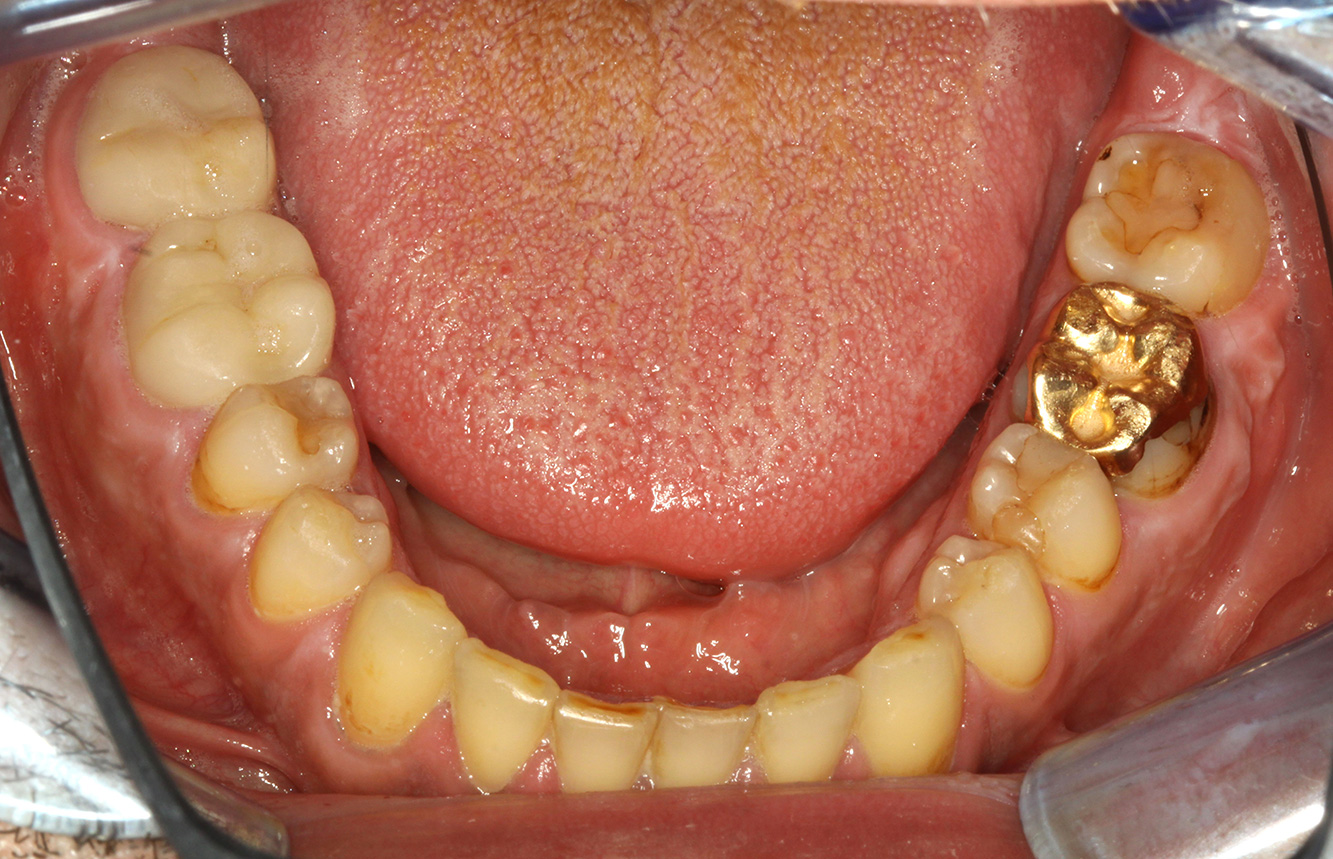

Der (mund)-gesunde Patient mit Implantaten

Der 55-jährige Patient gibt in der Anamnese an, keine Allgemeinerkrankungen zu haben und keine Medikamente einzunehmen. Die Lebensgewohnheiten des Patienten sind ebenfalls unauffällig. Der Patient hat einige zahnärztliche Restaurationen und zwei Implantate (2. und 4. Quadrant). Anhand der aktuellen Befunde lässt sich eine Gingivitis bei stabilem parodontalen Zustand am reduzierten Parodont (Stadium III, Grad A) feststellen. mehr Infos

Der gesunde Patient mit parodontaler Vorerkrankung & Periimplantitis

Ein 52-jähriger Patient stellt sich zur Präventionssitzung vor. Der Patient hat keine Allgemeinerkrankungen und nimmt keine Medikamente ein. Er hat verschiedene zahnärztliche Versorgungen und zudem zwei aktive kariöse Läsionen. Außerdem verfügt der Patient über vier Implantate (2., 3. und 4. Quadrant). Es zeigt sich eine parodontale Vorerkrankung (Stadium IV, Grad B). Derzeit herrschen stabile parodontale Verhältnisse, lediglich am Implantat regio 36 zeigen sich Sondierungstiefen (ST) von 5 mm. Zudem lässt sich eine Gingivitis feststellen. mehr Infos